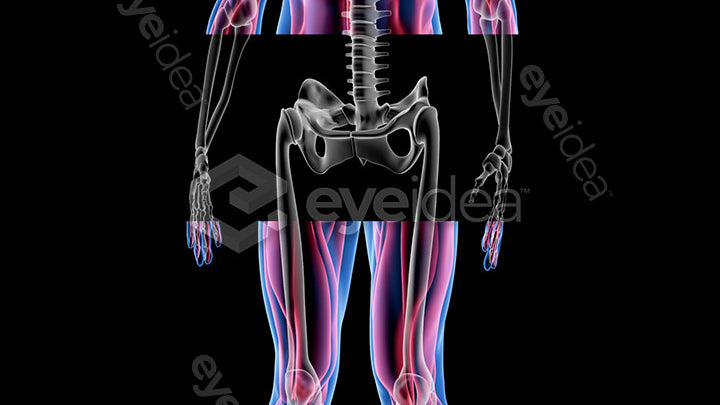

Our Stock-Packs™ are curated to include a varied

range of angles, motion, styles and formats,

ensuring that creators can find the assets

they want fast and easy.

Our stock videos, images, and animations come

with a wealth of experience spanning over two

decades, giving creators assurance

of premium quality assets.